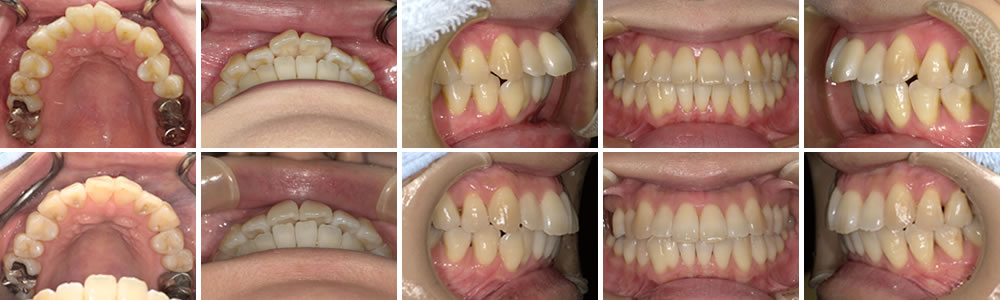

上顎前突の矯正治療例(30代女性 治療期1年7ヵ月)

上顎前突の治療例(Before&After)と解説

| 年齢・性別 | 30代女性 |

| 治療期間 | 1年7ヵ月(途中一時中断・再開) |

| 抜歯 | 無し |

| 治療費(税込) | 242,000円 |

| 備考 | 治療方法:上前歯部部分矯正(アライナー型矯正装置使用) |

上段が初診時写真となります。著しい上顎前歯部の前突が認められます。今回は目立たないように矯正したいとの希望があり、アライナー(マウスピース型)矯正装置を用いたアライナー矯正治療となりました。

今回のケースでは途中に治療の中断もあり、後戻りもあったために時間と個数が増えました。下段写真のとおり、上記の期間、個数で終了となりました。